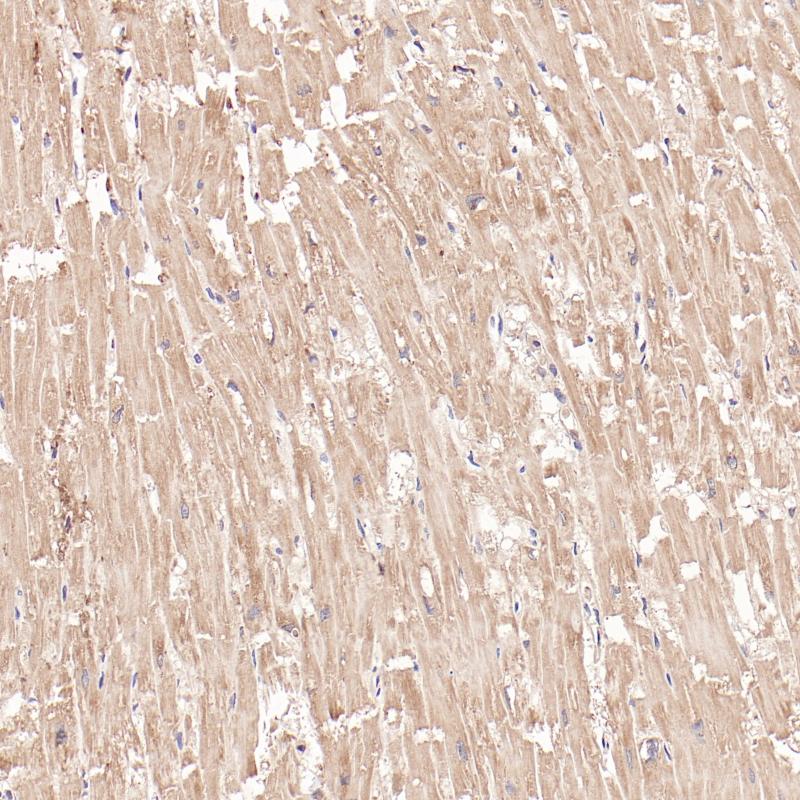

间变性淋巴瘤激酶(ALK)是一种酪氨酸激酶受体,通常在发展中的中枢神经系统和外周围神经系统区域内低水平表达。ALK可能通过多种机制在癌症中被激活,在间变性大细胞淋巴瘤、炎性肌成纤维母细胞瘤、横纹肌肉瘤、非小细胞肺癌等肿瘤中表达

阳性对照

非小细胞肺癌

亚细胞定位

细胞质/细胞核